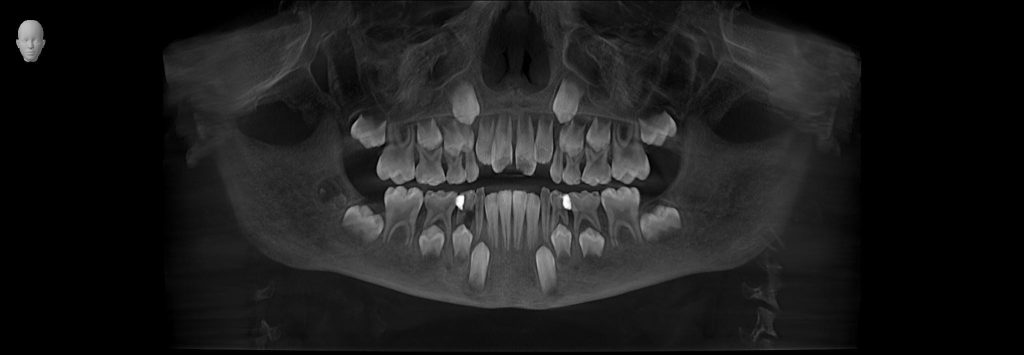

Dental & Jaw Findings

- Narrow upper jaw

- Crowding of upper front teeth

- Deep, high-arched palate

- Early crossbite

- Tongue resting low in the mouth

Diagnosis

Tatvik was diagnosed with:

- Airway-related maxillary constriction

- Pediatric sleep-disordered breathing

- Chronic mouth breathing habit

- Low tongue posture

- Early orthodontic malocclusion

2. Gentle Maxillary Expansion

A child-friendly expander was used to widen the upper jaw.

This helped to:

- Improve nasal airflow

- Create space for the tongue

- Reduce snoring

- Allow proper jaw growth

- Make room for teeth naturally

4. Early Orthodontic Alignment

Once the jaw was widened:

- Front teeth alignment improved

- Crossbite corrected

- Bite stabilized

- Facial growth guided in a healthier direction